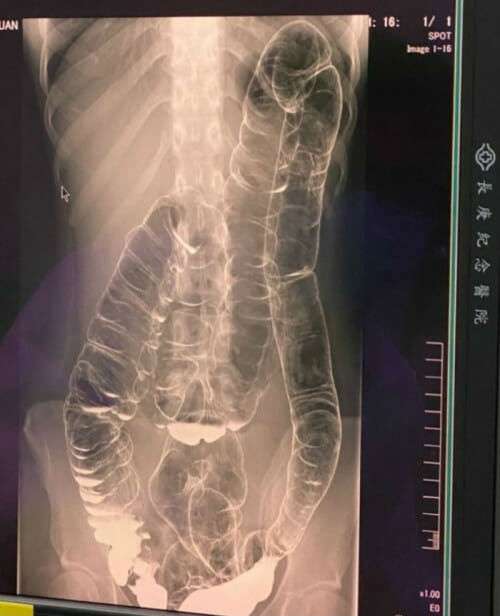

Rontgen Usus (Foto: World Of Buzz)

Setelah mengalami kondisi ini selama bertahun-tahun, akhirnya dia memutuskan mengunjungi dokter dan melakukan rontgen untuk melihat seberapa buruk organ pencernaannya.

Betapa terkejutnya, setelah hasil rontgen keluar, ternyata usus besarnya membengkak dan hampir menjepit bagian jantungnya.

Sembelit terjadi karena adanya penyumbatan feses di usus besar dan memungkinkan usus besar menyerap semua air sehingga membuat feses tersebut kering dan susah dikeluarkan.

Seringkali ketika ada penyumbatan feses yang berlebihan, usus besar akan meregang karena menampung banyaknya feses yang ada.